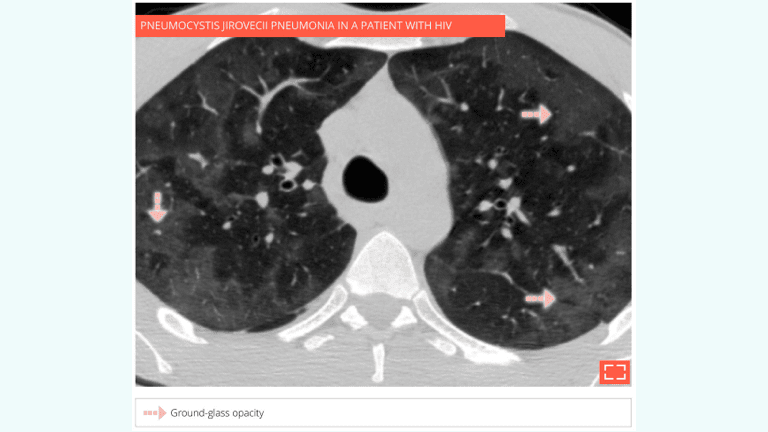

Ground-glass opacity

•  Slightly increased attenuation of lung parenchyma, with preservation of vascular and bronchial margins.

• Ground-glass opacity can be associated with various conditions:

• Pulmonary infection: pneumocystis jirovecii pneumonia, cytomegalovirus (CMV), etc.